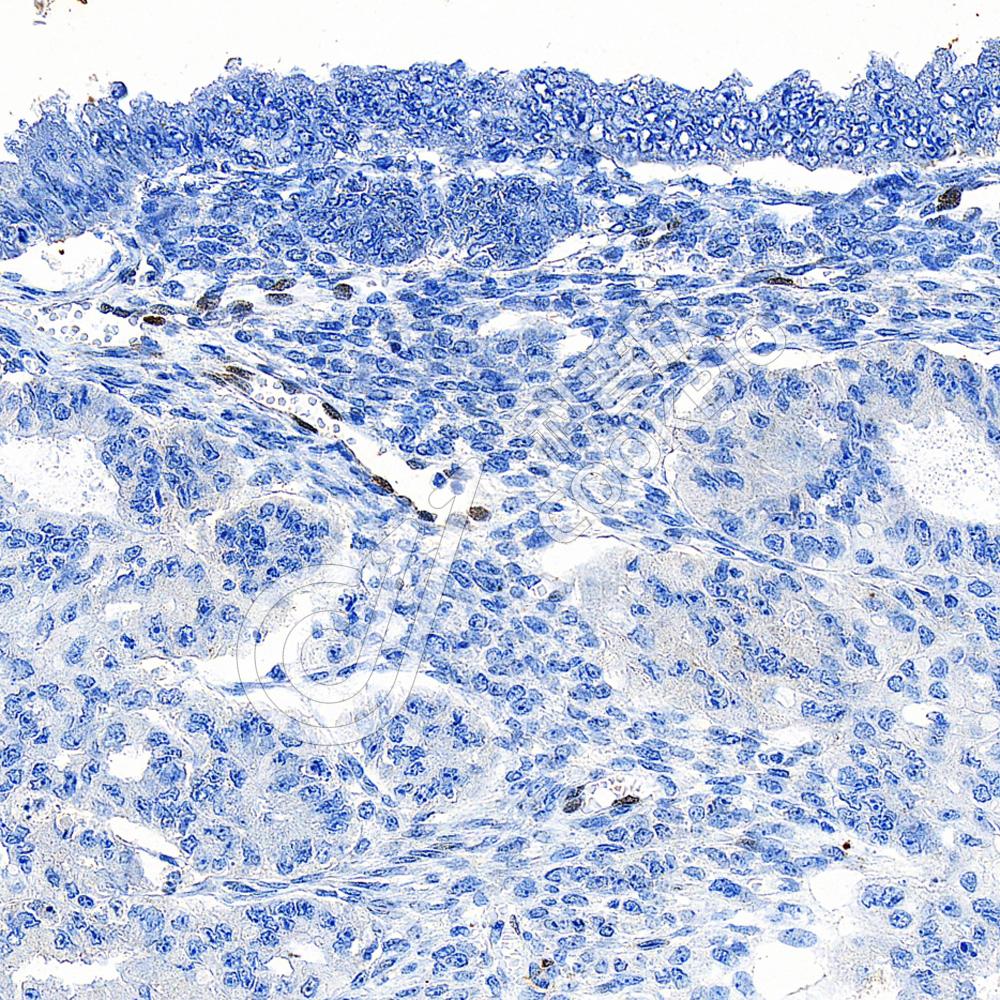

IHC检测FGF2蛋白(货号 K5461907).

样品: 人子宫内膜癌, 4%多聚甲醛 (货号KSG1101) 固定12-24小时.

抗原修复: Tris-EDTA抗原修复液(pH 9.0) (货号KSG1203), 水浴100℃, 25分钟.

—抗: 1: 1000稀释, 4℃ 孵育过夜.

二抗: S-vision免疫组化多聚二抗(山羊抗兔),即用型 (货号KB3906), 室温孵育20分钟.